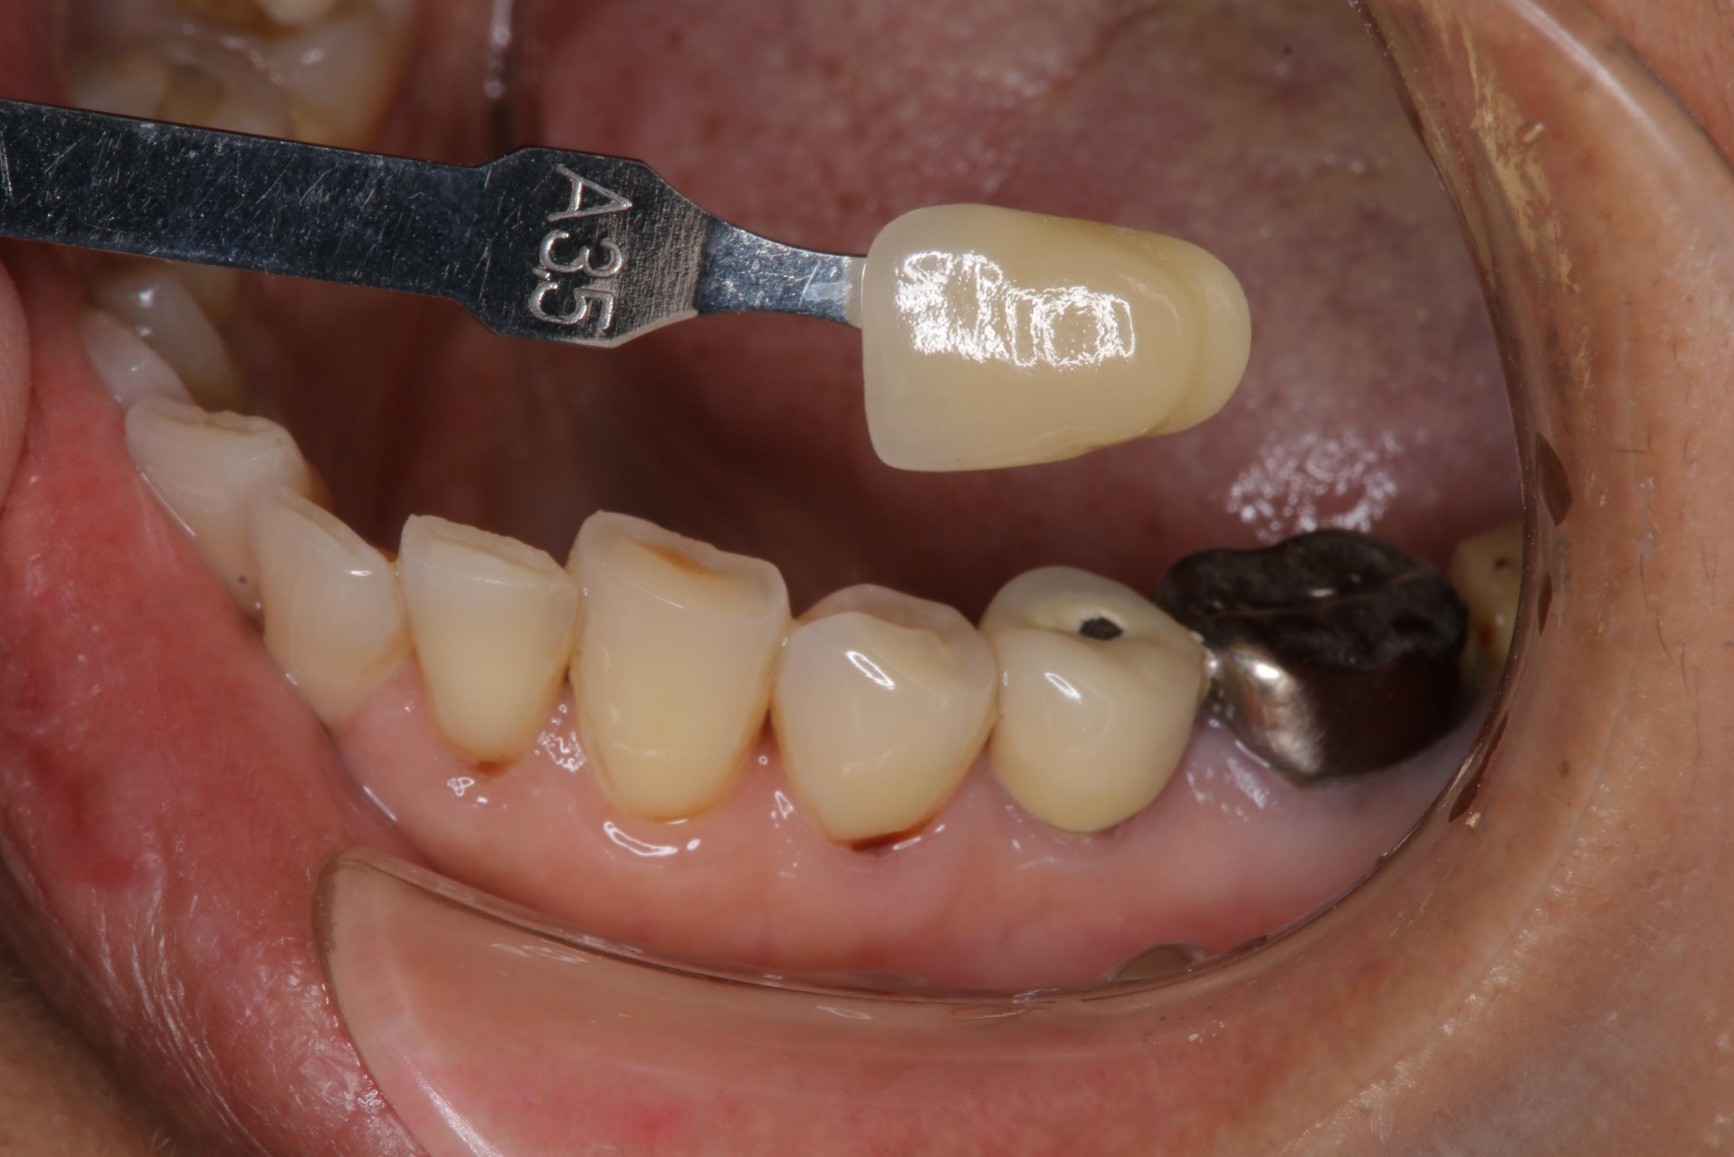

治療後,牙周咬合良好

治療後,密合度良好

術前、術後比較

幾年下來,這一類連續的治療,長期的癒後相當穩定,因此對於有心保留牙齒的患者,提供了另一個方法,是植牙之外的另一個重要的治療方式。